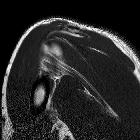

MRI. Conjoint

and intact tendon disc of teres minor and infraspinatus muscle.